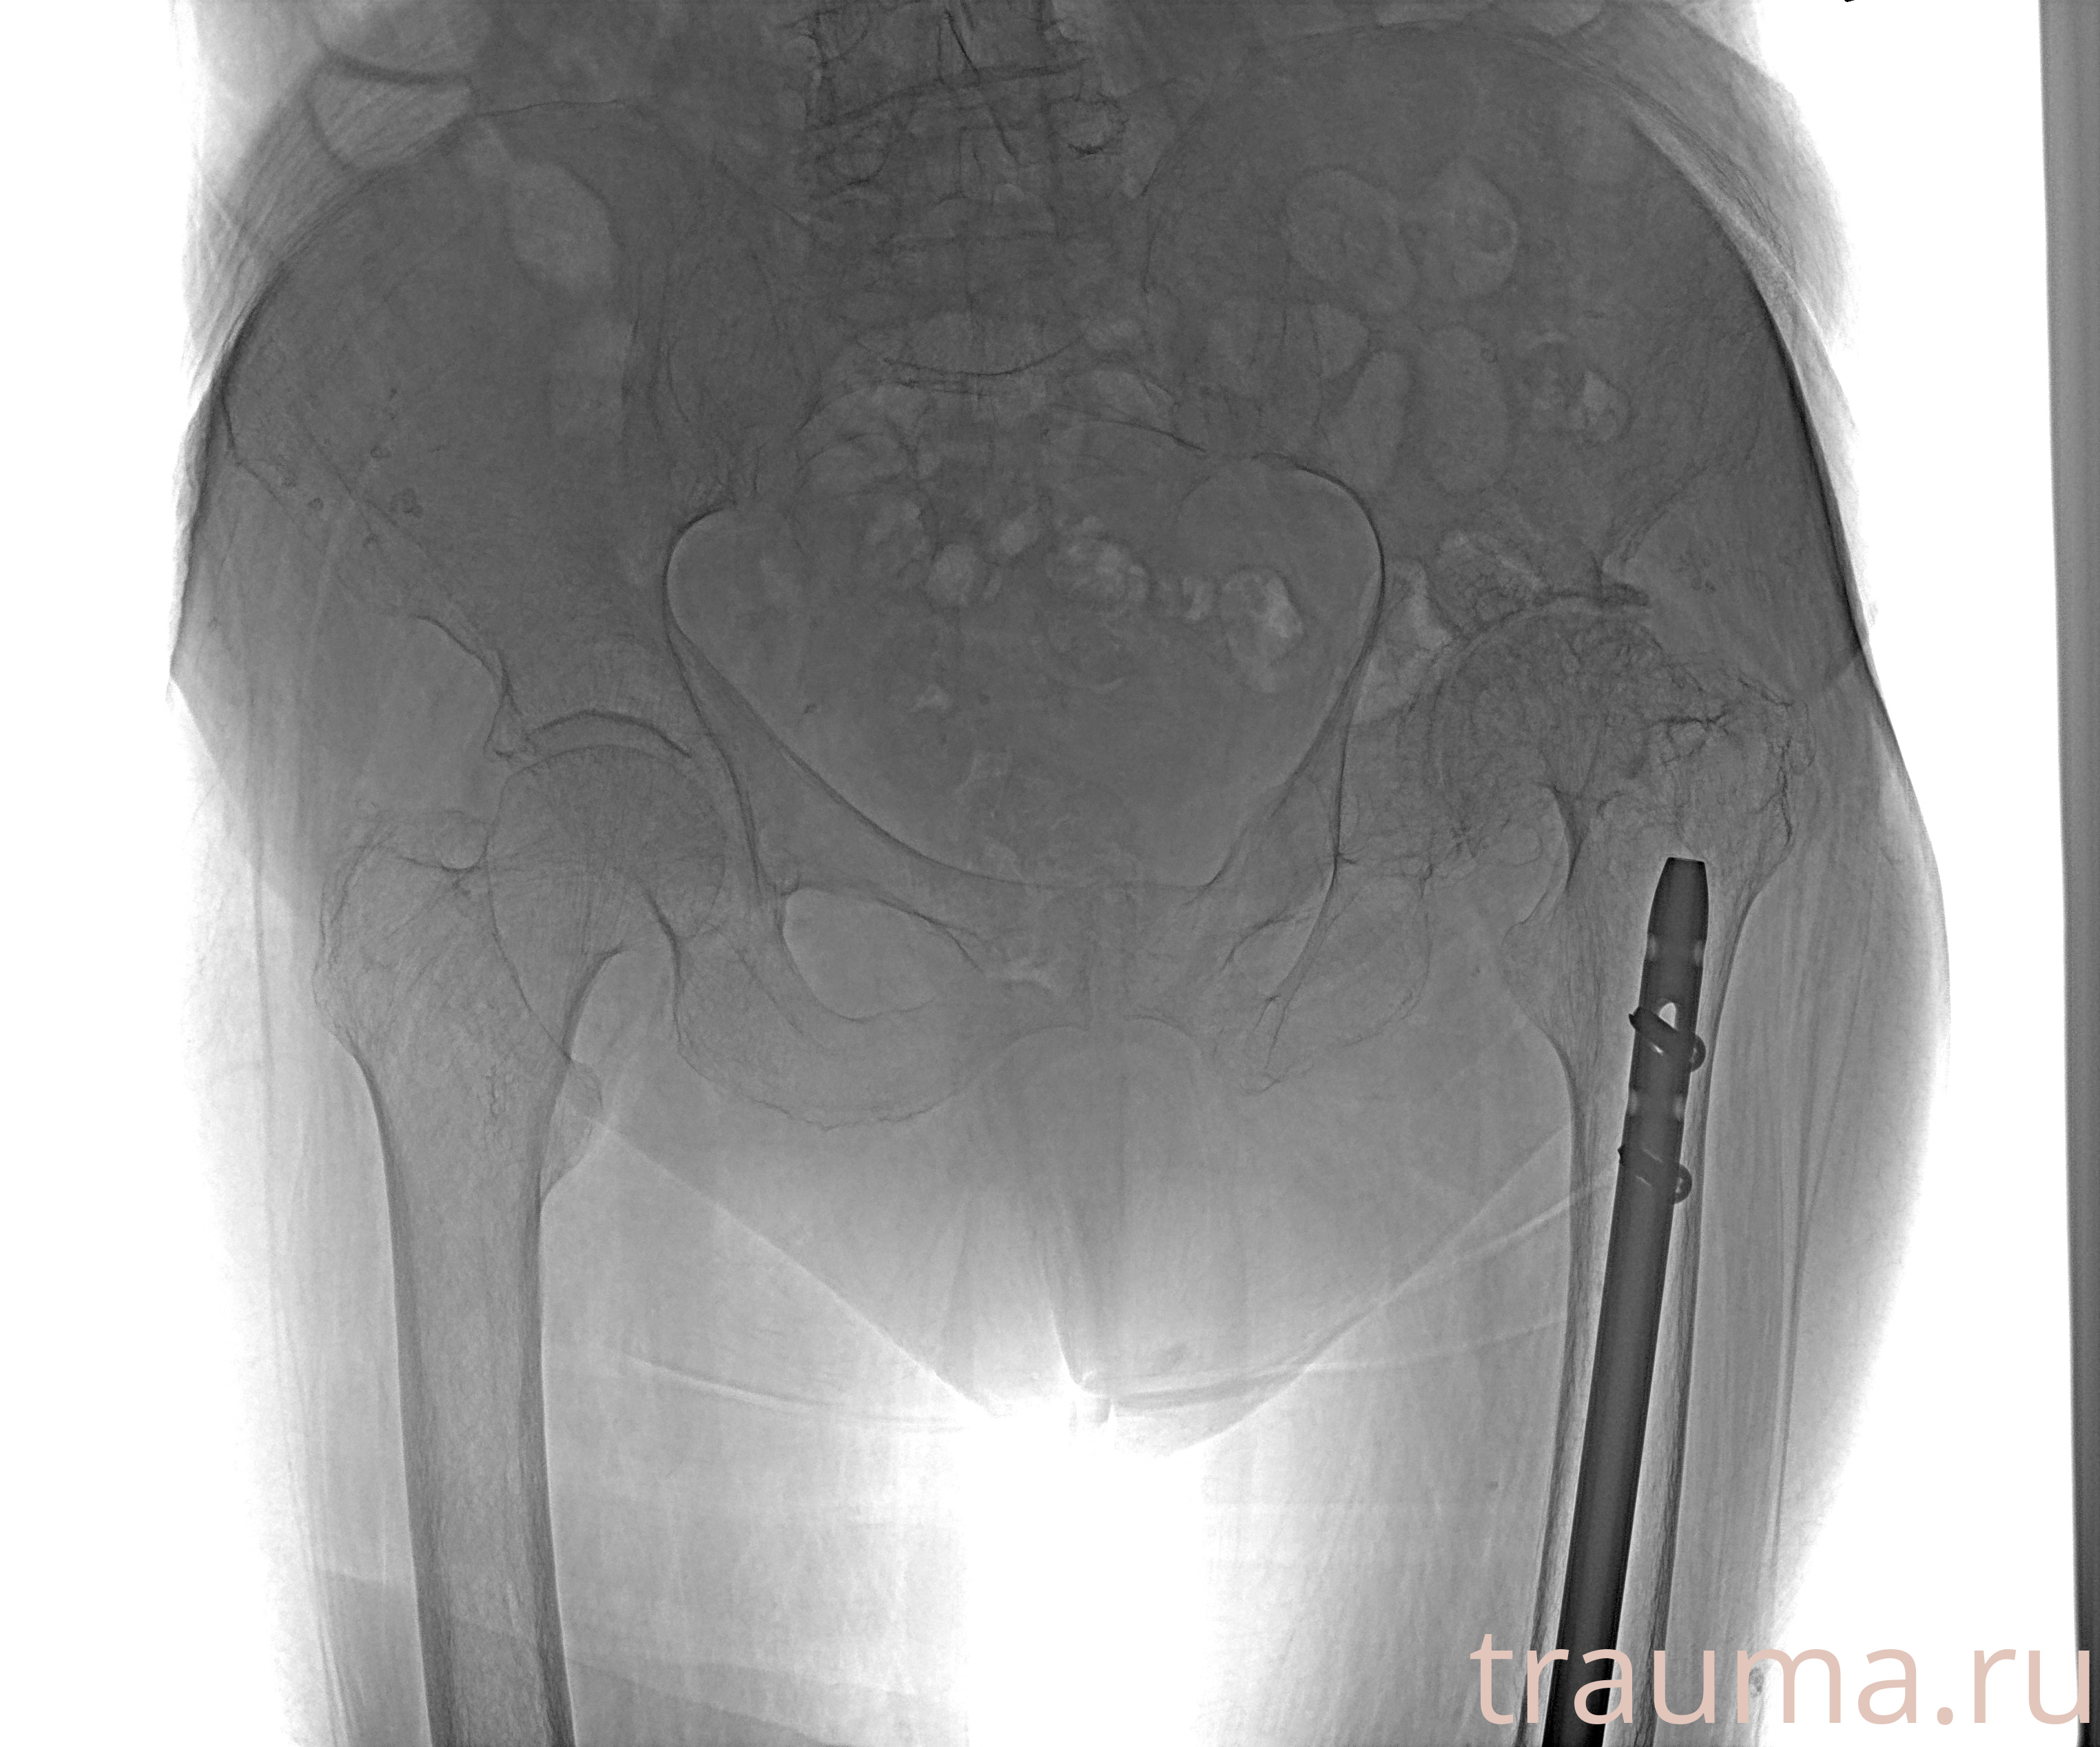

Перелом 3-5 ребер слева